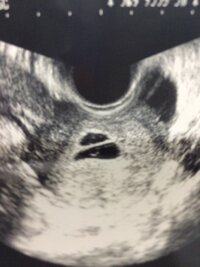

双子だとわかるのはいつ? 病院の検査で双子だとわかるのは 早くて妊娠5週の後半 です! 二卵性の双子の場合は、はじめての受診でわかることがほとんどです! 妊娠を確認するための超音波(エコー)検査で、胎嚢が二つ確認できれば双子だと確定され 無脳症はいつわかる? 先天異常とは、赤ちゃんが生まれつき持っている異常のことです。 ここでは、そんな 先天異常のなかでも、無脳症についてご紹介します。 無脳症とは具体的にどんな異常なのか、妊娠したらどの時期からわかるようになるのか妊娠5週目~7週目でわかる人が半数! 双子妊娠がわかった時の週数も尋ねたところ、 5週目~7週目でわかる人が半数 でした。

双子の妊娠っていつ分かるの? それではいよいよ、双子の妊娠がいつ分かるのか?という事について説明します。結論から言いますと、双子の妊娠は 早い人なら妊娠5週ぐらいで分かります。 半数以上の妊婦の方が、初回の妊婦検診で妊娠が分かっています 双子妊娠発覚! いつわかる? リスクは? まとめ 突然の双子や三つ子ちゃんの判明で動揺された方が多いと思います。 育児は確かに想像通り大変ですが、 やっぱり赤ちゃんが並んでいるところや遊んでるところを見ると癒されるし、可愛さも2倍以上 双子の妊娠発覚はどのタイミングでわかるの? 私の場合は、妊娠5週目で『胎嚢 (たいのう)=赤ちゃんのベッドのようなもの』を見つけました。 1回目の検診では、1つの胎嚢の確認で単胎児